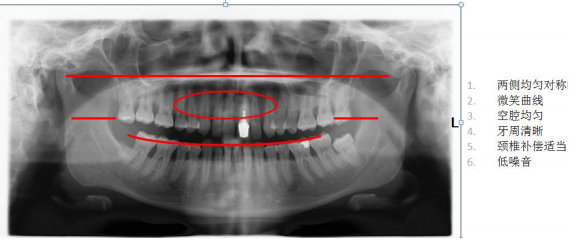

其他全景機前牙掃描層厚較窄,定位困難。 CRANEX CRA-2 前牙掃描層厚增加 50%,提高前牙區(qū)圖像質(zhì)量,定位精準 成人全景:顯示上下牙列、牙槽骨、神經(jīng)管及 TMU,圖像均勻,前牙區(qū)結(jié)構(gòu)也可清晰顯示

前牙掃描層增厚技術(shù)與傳統(tǒng)的前牙掃描攝影技術(shù)相比,提高了病人前牙區(qū)圖像質(zhì)量,利用幾何學(xué)原理和 最佳的光束方向, 能產(chǎn)生連續(xù)的圖像, 掃描出清晰的上下頜骨.鼻副竇及顳下頜關(guān)節(jié)結(jié)構(gòu). 2) 高靈敏度 CCD 探測器: 高清 CCD 探測器,實現(xiàn)空間分辨率 6.25lp/mm 呈現(xiàn),清晰呈現(xiàn)細微結(jié)構(gòu)影像。 3) 窄光束技術(shù):采用 0.5mm 小焦點,高性能準直器 Slit beam 及小焦點技術(shù)使圖像高度清晰. 4) 獨特的高穩(wěn)定性 DC 反饋控制系統(tǒng): 曝光時如果輸入電壓有所波動, 采用 DC 反饋控制系統(tǒng),使 X 線球管電 壓及電流保持恒定. 5) 具有曝光脊椎自動補償功能, 可減少脊椎及頸部贅肉對圖像的影響,而不影響圖像其他部分.從而提高圖像的 清晰度. (二) 快速全景掃描,減少移動偽影,提供最佳圖像質(zhì)量和最低劑量 ? 快速全景掃描提供極佳圖像質(zhì)量 ? 成人快速掃描僅需 9 秒 ? 兒童快速掃描僅需 8 秒 ? 僅需三步,即可快速完成操作 (三) 定位最精準,拍攝最便捷 1) 依靠獨特的五點頭部定位系統(tǒng)及三光束定位系統(tǒng),實現(xiàn)準確的三維立體定位. ? 三盞激光定位燈——定位準確 ? 專利技術(shù)五點頭顱定位裝置,定位穩(wěn)定 ? 開放式設(shè)計 2) 直觀的控制面板 (四) 智能投照選擇及劑量控制技術(shù)——操作者不需選擇任何攝影條件就可以實現(xiàn)精準掃描 ? 專利的自動曝光劑量控制(AES),根據(jù)頭部定位支架所測量的病人頭部寬度,自動調(diào)節(jié) KV 值,通 過智能曝光負反饋系統(tǒng),實現(xiàn)低劑量下的最精準的曝光控制。 ? 自動準直器選擇(ACS),可以根據(jù)病人類型不同,拍攝范圍 FOV 不同,自動選擇準直器實現(xiàn)曝光 控制。 ? 自動曝光控制(AEC),通過自動感應(yīng)單元反饋電路,實現(xiàn)自動曝光參數(shù)控制 ? 具有曝光脊椎自動補償功能, 可減少脊椎及頸部贅肉對圖像的影響,而不影響圖像其他部分.從而提 高圖像的清晰度. (五) 結(jié)構(gòu)緊湊,完全不受機房空間限制 ? 僅 1.5*2 平方米的裝機面積即可滿足要求 ? 重量為 100KG, 重量大,穩(wěn)定性高 (六) 具有功能豐富發(fā)應(yīng)用軟件,可以進行病例輸入、病例搜索、圖像放大、圖像增強、負像,長度、密度、角度測量,進行模擬種植等、可以進入醫(yī)院的 PACS 系統(tǒng)。